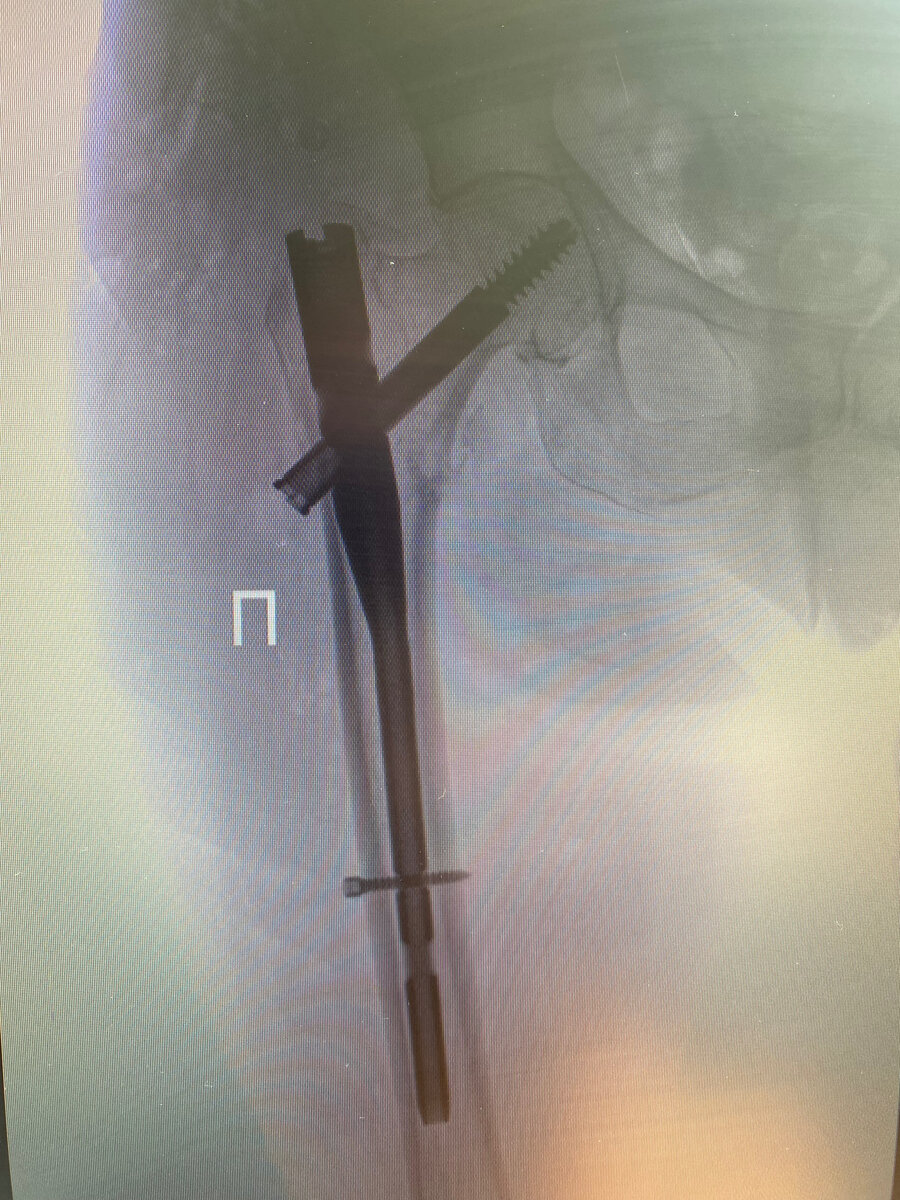

Интрамедулярный стержневой остеосинтез бедренной кости

Суть данного остеосинтеза(операции) заключается в том, чтобы поставить внутрь бедренной кости штифт, а в головку бедренной кости поставить шеечный винт, который проходит через тот самый штифт и шейку бедра и тем самым стабилизирует перелом. Обычно эту операцию выполняют через три небольших разреза по наружной поверхности бедренной кости.

интрамедулярный стержневой  остеосинтез у пациентки 101 года(кость на удивление была в отличном состоянии)